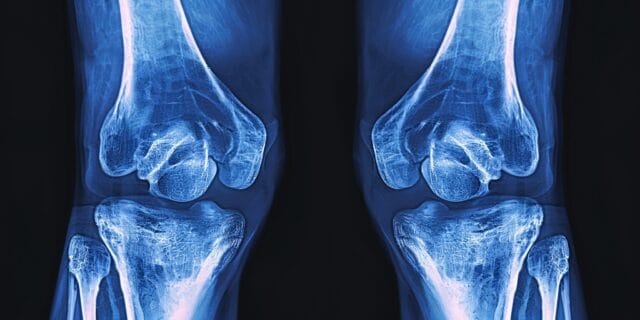

Diagnosis of MCL Injuries

Diagnosing an MCL injury starts with a medical history review and a physical examination. This process involves evaluating symptoms, understanding the history of the injury, examining the knee for structural integrity, and comparing the injured knee to the non-injured knee. Other tests include:

- X-Ray: X-ray images do not detect injuries to the MCL directly; however, they can reveal presence of broken bones or other injuries in the knee.